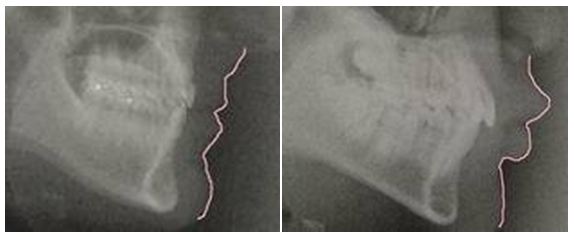

在評估縮唇手術時,牙齒的位置很重要,所謂「唇齒相依」。下左圖是理想的齒列及嘴唇位置。下右圖的上下牙齒往前突,嘴唇因此也被頂出去。牙齒矯正後,外突的嘴唇也會得到改善。下巴後縮的人嘴唇看起來也會較厚,此時做隆下巴會比縮唇重要。